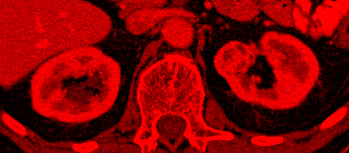

Red Channel: Structure

Red Channel Image

Morphological Structure

Acts as the structural foundation, establishing the general shape and physiological context of the organ.